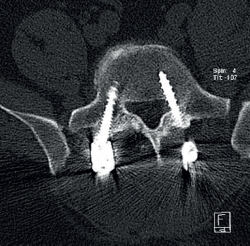

Cincuenta días tras el accidente se realizó fusión lumbar instrumentada L4-L5 con inserción de dispositivo intersomático por vía transforaminal derecha. En el segundo día postoperatorio presentó empeoramiento del dolor, objetivándose en la tomografía computarizada (Figura 2) malposición del tornillo L5 izquierdo que invadía el canal. Se reintervino a los 5 días corrigiendo el trayecto del tornillo. Sin embargo, persistió el dolor. La revaluación del caso, sumada a los hallazgos de EMG, motivó estudios complementarios de pierna y trayecto ciático (Figuras 3 y 4), detectándose una masa tumoral en el fémur izquierdo compatible con sarcoma fusocelular.

retla.08216.fs2508016-figura2.png

Figura 2. Tomografía computarizada lumbar postoperatoria en corte axial. Tornillo pedicular izquierdo de L5 mal posicionado, con violación de la pared medial del pedículo e invasión parcial del canal vertebral.